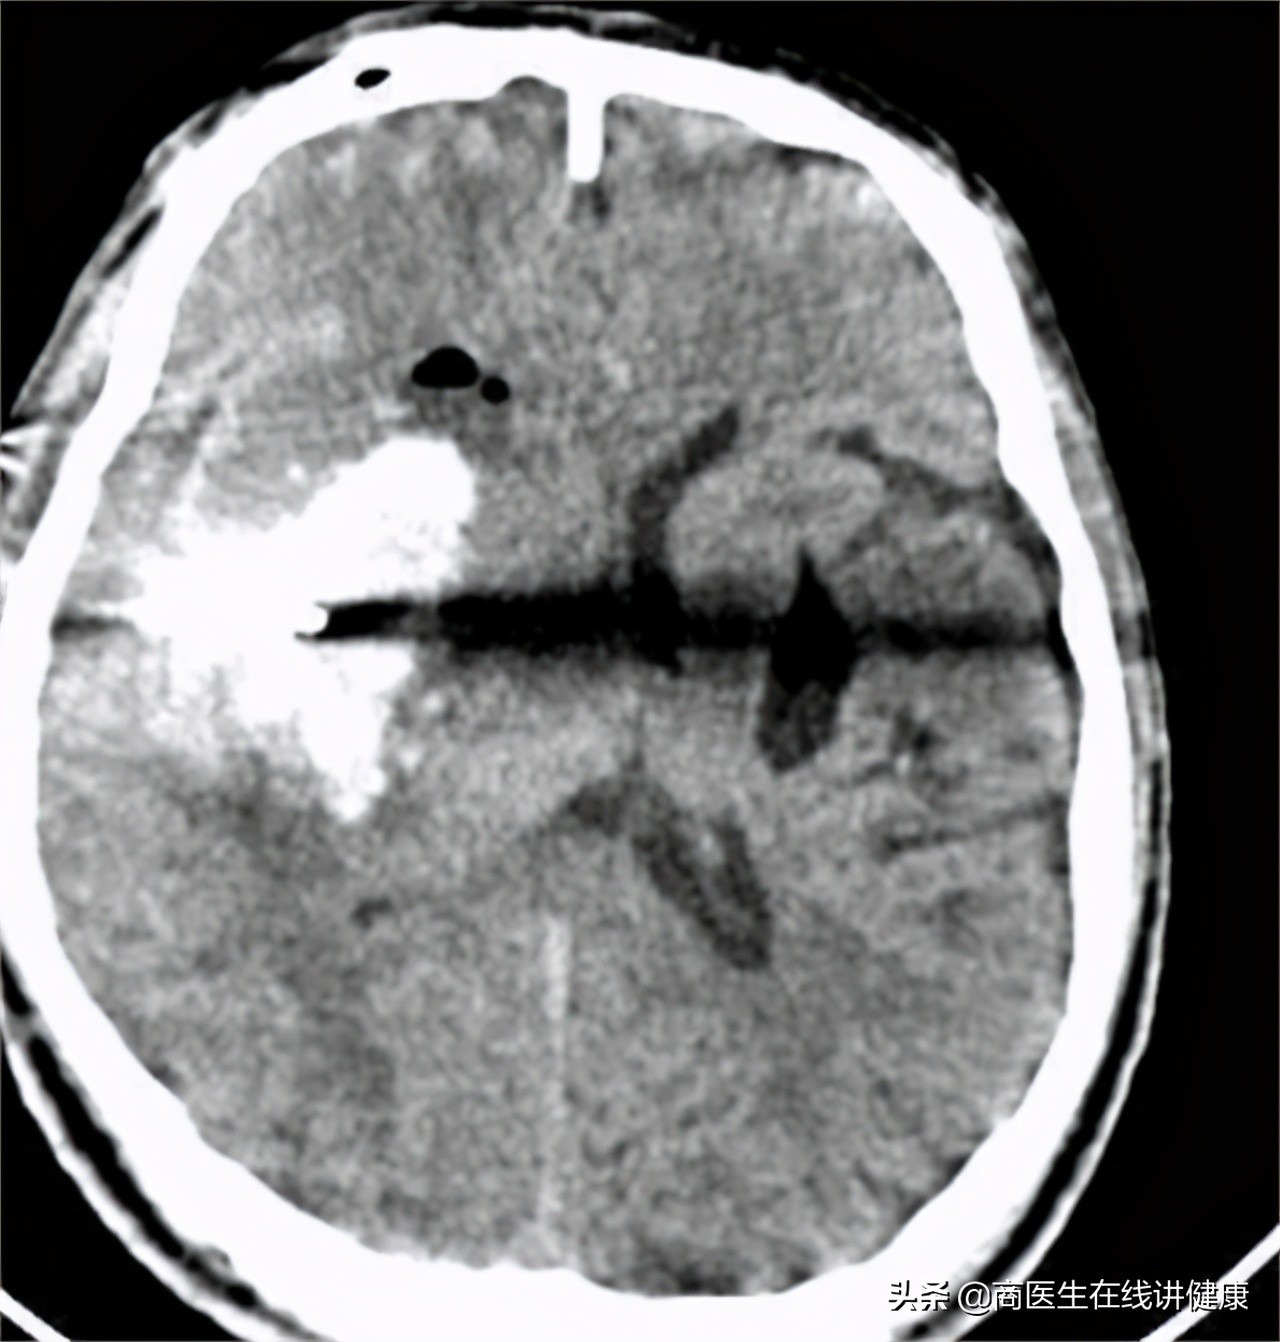

医生检查了付先生的基本情况后,做了脑部CT等常规检查,确诊付先生是突发出血性的脑中风,即脑溢血。鉴于送医及时,脑部出血量不大,医生紧急为付先生做了脑部止血和引流的手术,帮助付先生脱离了生命危险,将其送往加护病房观察情况。

患者体温36.1℃、血压160/100、身高184cm、体重102kg。患者查体意识不清,无法正常交流,嘴角伴有褐色呕吐物。查头CT示:右侧小出血性脑中风,量约8ml,脑动脉硬化性白质脑病,左侧基底出血,可诊断为突发性出血性脑中风。